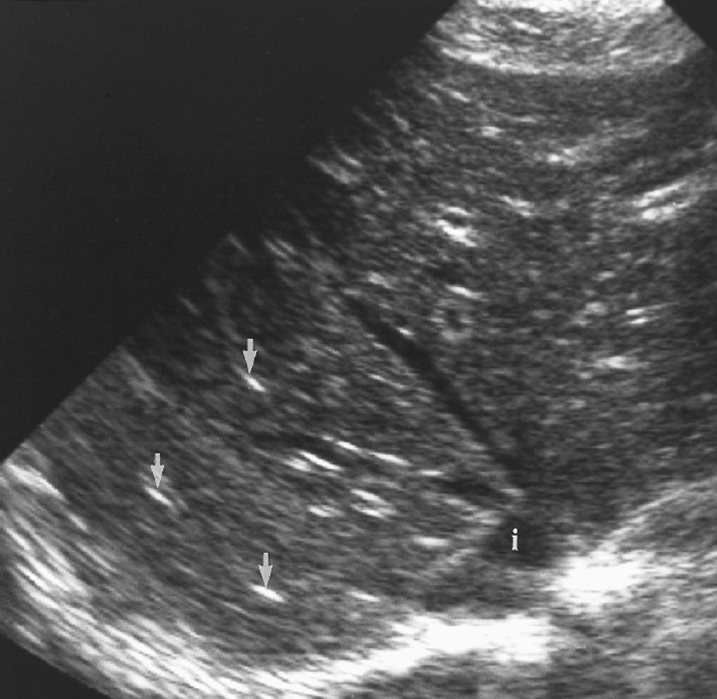

cirrhosis sonographic characteristics

isoechoic regenerative nodules

decreased visualization of vascular structures

cirrhotic liver with ascites

cirrhotic liver

fibrosis and altered architecture of cirrhosis cause a

coarse appearance

inspection of liver surface with what kind of probe demonstrates nodularity

high frequency, linear array